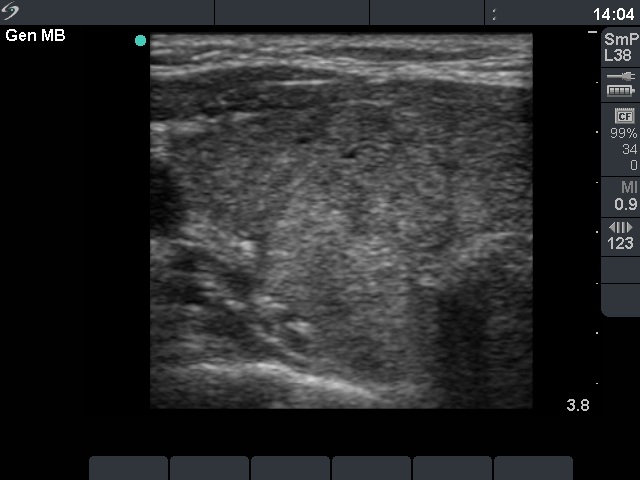

Ultrasonography: a moderately hypoechogenic thyroid was found with multiple circumscribed lesions divided by fibrous tissue. One of these areas contained hyperechogenic granules and exhibited increased vascularization.

The US pattern of this patient highly resembles that of the so-called micronodular form of Hashimoto's thyroiditis. The "nodules" in this case are in truth pseudolobules of the lobes. The prominent appearance of the fibrous tissue dividing the lobules resembles a capsule of a follicular adenoma. In contrast with the latter, not only one or two, but numerous circumscribed areas are present in this case.